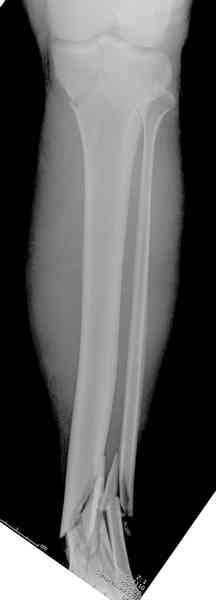

При высокоскоростных переломах редко можно встретить изолированную травму пилона, и в моей практике изолированные травмы большая редкость, поэтому, как дополнение к обсуждаемой теме, решил представить свежий, двухдневной давности случай.

Предыдущей сменой до 4:00 утра по поводу открытого перелома бедра, тибиал плато, пилон и надколенника сделана операция.

Пострадавшему 21 г., травма скоростная, после I&D с расширением раны, на бедре сделана операция ретроградным интрамедуллярным штифтом, остеосинтез с частичной резекцией надколенника и ушивание собственной связки.

На голень наружный фиксатор, рану на бедре ушили (рана была изнутри кнаружи всего 2 см). По протоколу травматических больных, до операции обследован ангиографически, (у больного дистально не смогли определить пульсацию) сосудистый хирург подтвердил проходимость на всем протяжении магистрального сосуда нижней конечности по снимкам ангиограмм.